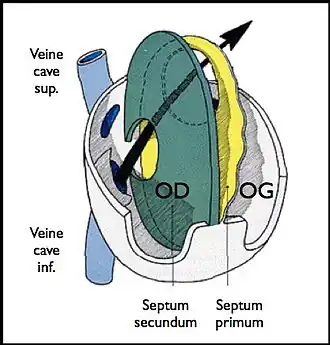

Le foramen ovale est un passage en forme de fente « en chicane » entre les deux constituants principaux de la cloison inter-auriculaire, le septum primum du côté gauche et le septum secundum du côté droit. Il fait communiquer les deux atriums. Il tend à être fermé par une membrane (« la membrane du foramen ovale ») qui n'est maintenue en position ouverte que par la différence de pression régnant dans les atriums.